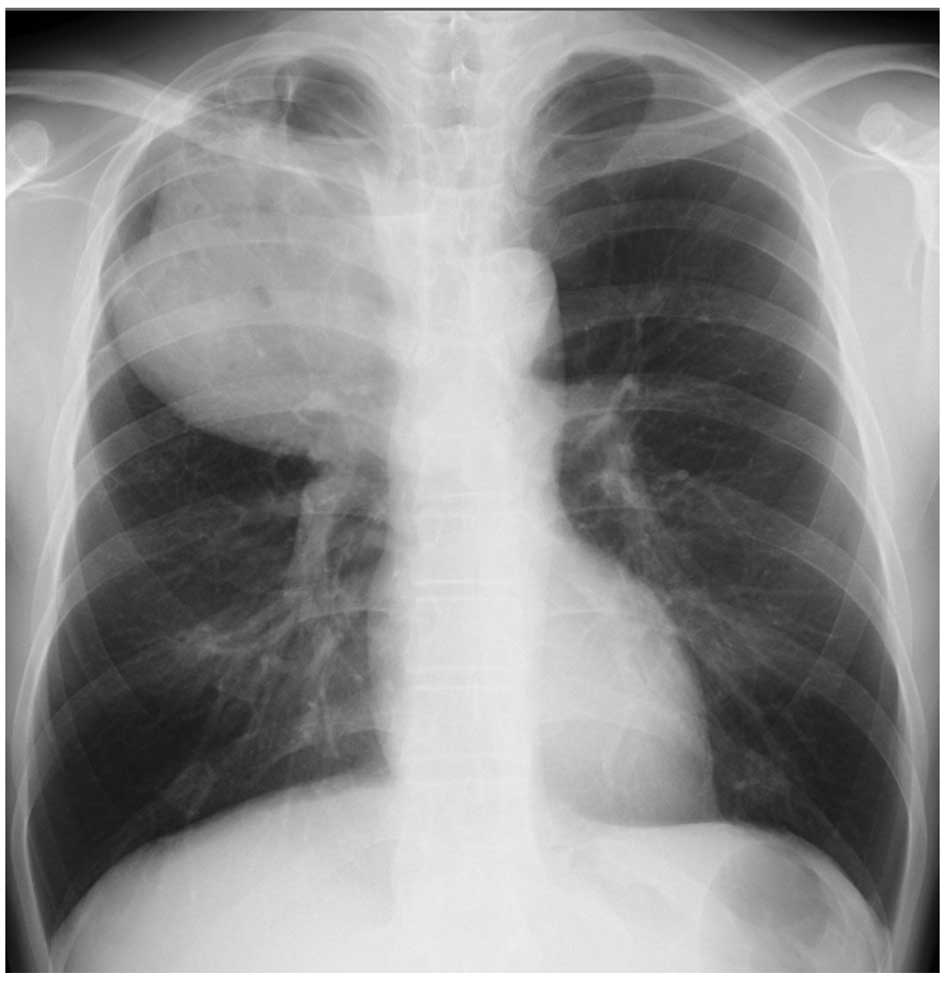

A 46-year-old man was admitted to the hospital with anorexia, fever and weight loss. The blood tests revealed a white blood cell count (WBC) of 22,900/µl with 78% neutrophils, a red blood cell count of 399×104/µl, and a platelet count of 43.2×104/µl. The patient's hemoglobin concentration was 11.5 g/dl and the hematocrit was 34.8%. On the blood chemistry tests, the serum albumin was 2.9 mg/dl, the alkaline phosphatase 348 U/l, the total bilirubin 0.3 mg/dl, and the creatinine 0.57 mg/dl. The serum transaminase levels were within normal limits, and blood serology revealed a C-reactive protein (CRP) level of 15.64 mg/dl. The granulocyte/colony-stimulating factor (G-CSF) level was 246 U/l (normal, ≤39 U/l). A sizeable mass was identified in the upper lobe of the right lung by chest radiography (Fig. 4). A biopsy specimen obtained by video-assisted thoracoscopic surgery revealed a poorly differentiated lung carcinoma. The patient received 4 courses of chemotherapy with carboplatin (AUC=5, day 1, q28 days), pemetrexed (500 mg/m2, day 1, q28 days) and bevacizumab (15 mg/kg, day 1, q28 days), followed by chemoradiotherapy (60 Gy). WBC decreased to within the normal range and fever subsided tentatively for several weeks after each course of chemotherapy. The response was evaluated as ‘stable disease’.